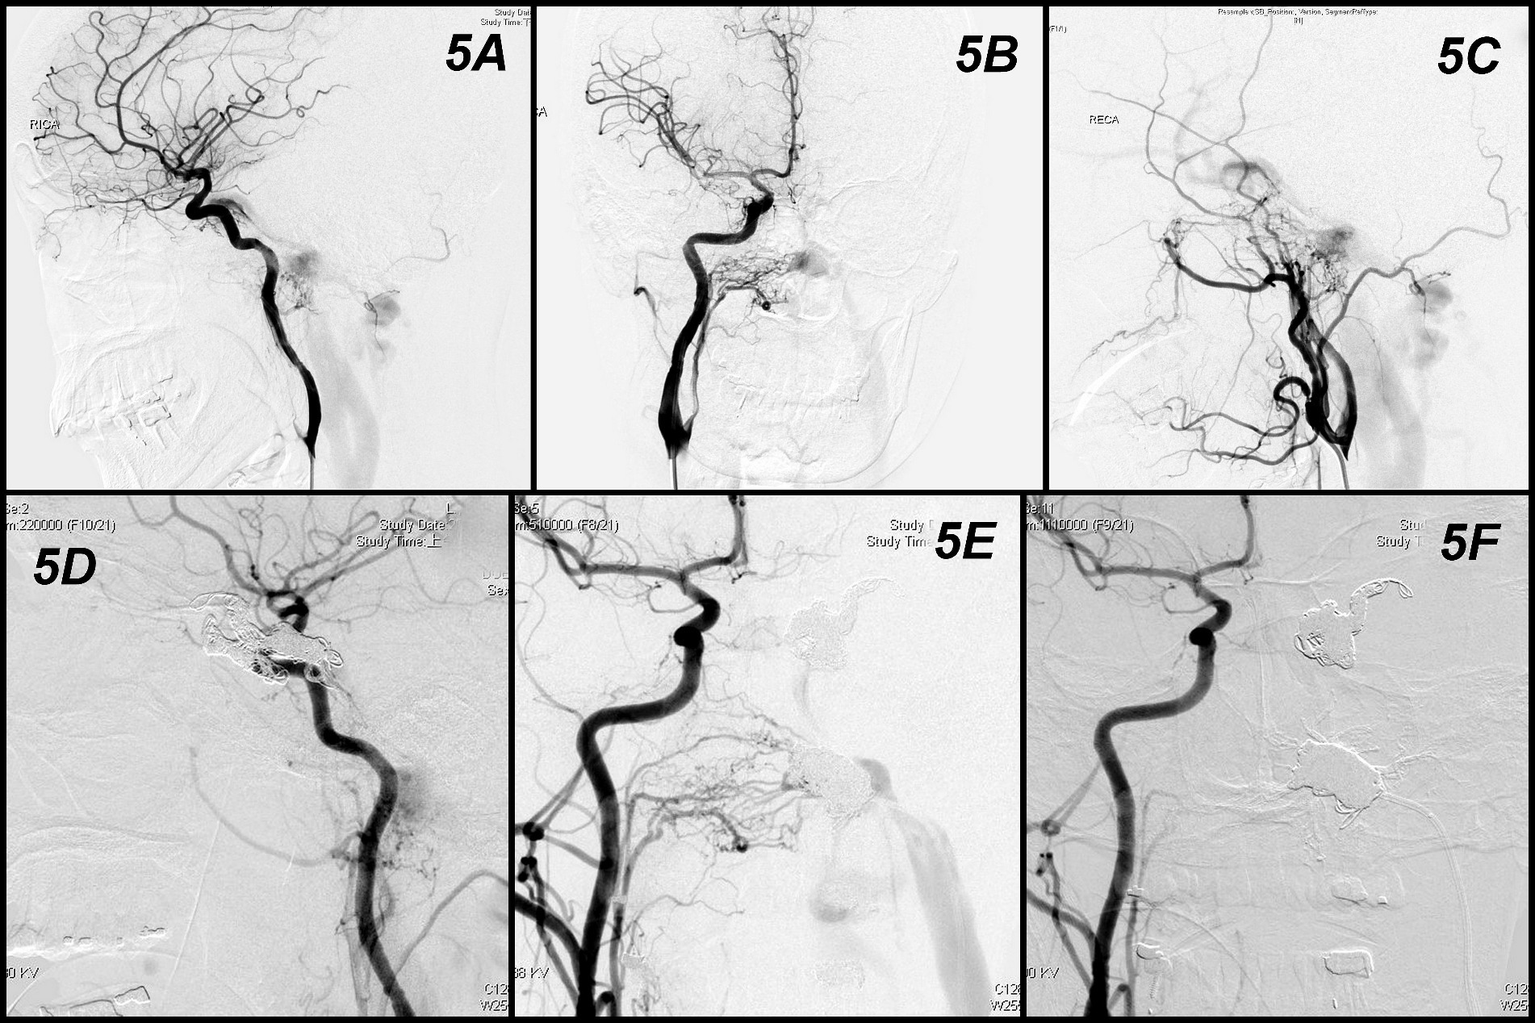

A female in the mid-forties (Case 14 in Table 1) suffered from headache, pulsatile tinnitus, and left facial palsy. Angiography found two DAVFs (Figure 5A). One left hypoglossal canal AVF, which was supplied from bilateral ascending pharyngeal arteries and occipital arteries; drained to internal jugular vein and inferior petrosal sinus (Figures 5B,C). Another left cavernous sinus DAVF was supplied from bilateral ICAs and MMAs with retrograde flow to middle cerebral vein and superior ophthalmic vein (Figures 5A,C). Compete embolization of the left cavernous sinus first by detachable coils (Figure 5D). Microcatheter later shifted to hypoglossal canal and did coils embolization. However, persistent flow of fistula despite dense packing by 9 coils in the hypoglossal canal (Figure 5E). The 1.2 mL Onyx was used to completely occlude the fistula (Figure 5F). The patient’s tinnitus was ceased immediately after procedure and facial palsy gradually improved within 3 months.

Figure 5

Angiographic findings and results obtained in Case 5. Two DAVFs (A). One at left hypoglossal canal supplied from bilateral ascending pharyngeal arteries and occipital arteries and drained to internal jugular vein and inferior petrosal sinus (B,C). Another left cavernous sinus DAVF supplied from bilateral ICAs and MMAs with retrograde flow to middle cerebral vein and superior ophthalmic vein (A,C). Compete embolization of the left cavernous sinus first by detachable coils (D). Persistent flow of fistula despite dense packing by coils in the hypoglossal canal (E). The Onyx was used to completely occlude the fistula (F).